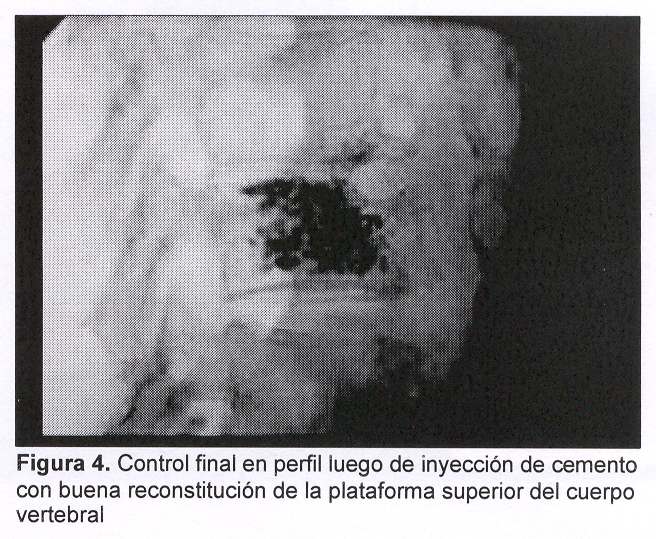

Se procedió a realizar vertebroplastia percutánea de L3 bipedicular mediante técnica ya descripta utilizando tungsteno como contraste (figura 4).